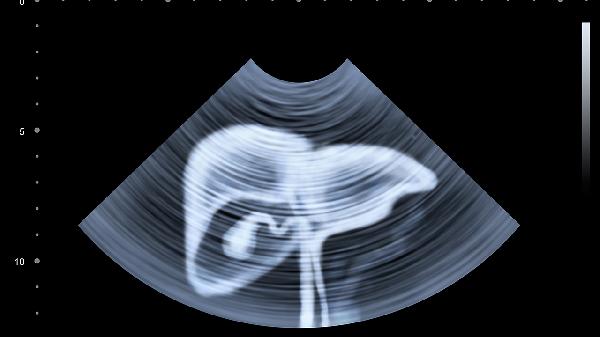

4、影像学检查如超声、CT或MRI可用于评估肝脏结构和形态,帮助发现肝硬化、肝癌等并发症。丙肝感染可能导致肝脏纤维化或硬化,影像学检查能直观显示肝脏变化,辅助诊断和评估病情。建议在确诊丙肝后进行影像学检查,特别是病毒载量高或肝功能异常者。